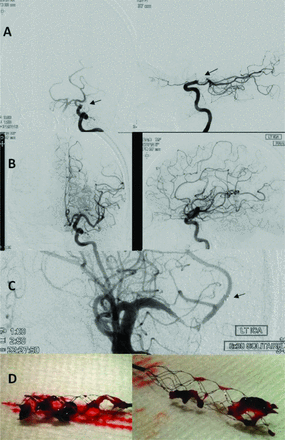

NIH卒中量表(署)得分是22。静脉注射重组组织纤溶酶原激活物(rtPA)管理,没有改善他的署得分。病人被送往angio-suite用纸牌和治疗设备。(A)基线左颈内动脉(ICA)血管造影前后的(美联社)和横向预测完成颈终点站闭塞远端沟通后动脉的起源(箭头);(B)最终美联社和侧ICA血管造影,2通过stentreivers后,完全再通;(C)美联社留给ICA运行开放stentreiver(6毫米×30毫米)和远端标记(箭头);(D)检索到的凝块第一次(左)和第二次传球后(右)的设备。在最后3个月,署分数去6和夫人分数提高到3。